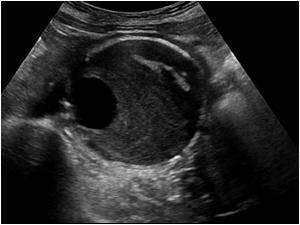

Abdominal Aortic Aneurysm is a focal dilatation of the Aorta caused by degeneration of the tunica media (middle connective layer of the arterial wall).

- Saccular – spherical in shape, appear like a pouch or sac from the vessel and are often filled with thrombus within the arterial wall (intramural)

- Fusiform – Dilatation that spans a larger length of the vessel